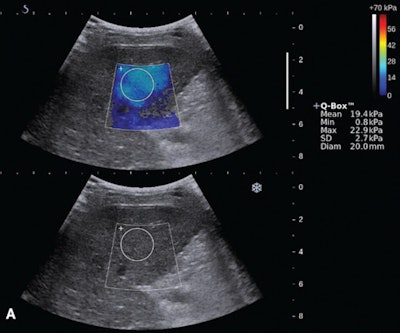

The researchers analyzed 103 patients with compensated cirrhosis. Of these patients, 63 had grade F0 varices (no varicose appearance), while 27 had F1 varices (straight, small-caliber varices), and 13 had grade F2 (moderately enlarged, beady varices) or F3 varices (markedly enlarged, nodular, or tumor-shaped varices). All patients received shear-wave elastography on an Aixplorer ultrasound scanner (SuperSonic Imagine) with a SC6-1 convex broadband probe for measuring liver stiffness.

After conventional sonography was performed, liver stiffness was measured by three abdominal radiologists with six to 17 years of clinical experience in abdominal radiology and liver sonography. The radiologists were blinded to the patients' clinical and endosopic results. Endoscopy was performed by two experienced upper gastroenterologists within one month before or after the shear-wave elastography exam.

The team calculated the optimal tissue stiffness cut-off value for predicting the presence of esophageal varices was 13.9 kPa; the optimal cut-off value for high-risk varices was 16.1 kPa. After performing receiver operating characteristic (ROC) analyses to determine diagnostic performance, the researchers found that liver stiffness (determined by shear-wave elastography) produced the highest area under the curve for both predicting esophageal varices in general, as well as specifically for high-risk esophageal varices.